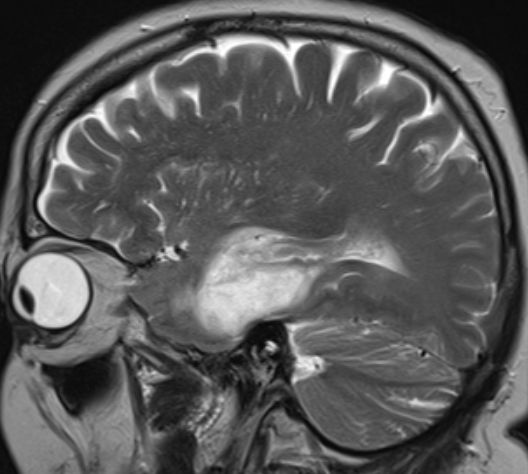

64-jährige Frau mir generalisierten Krampfanfällen und Hemiparese links.![]() | ||||